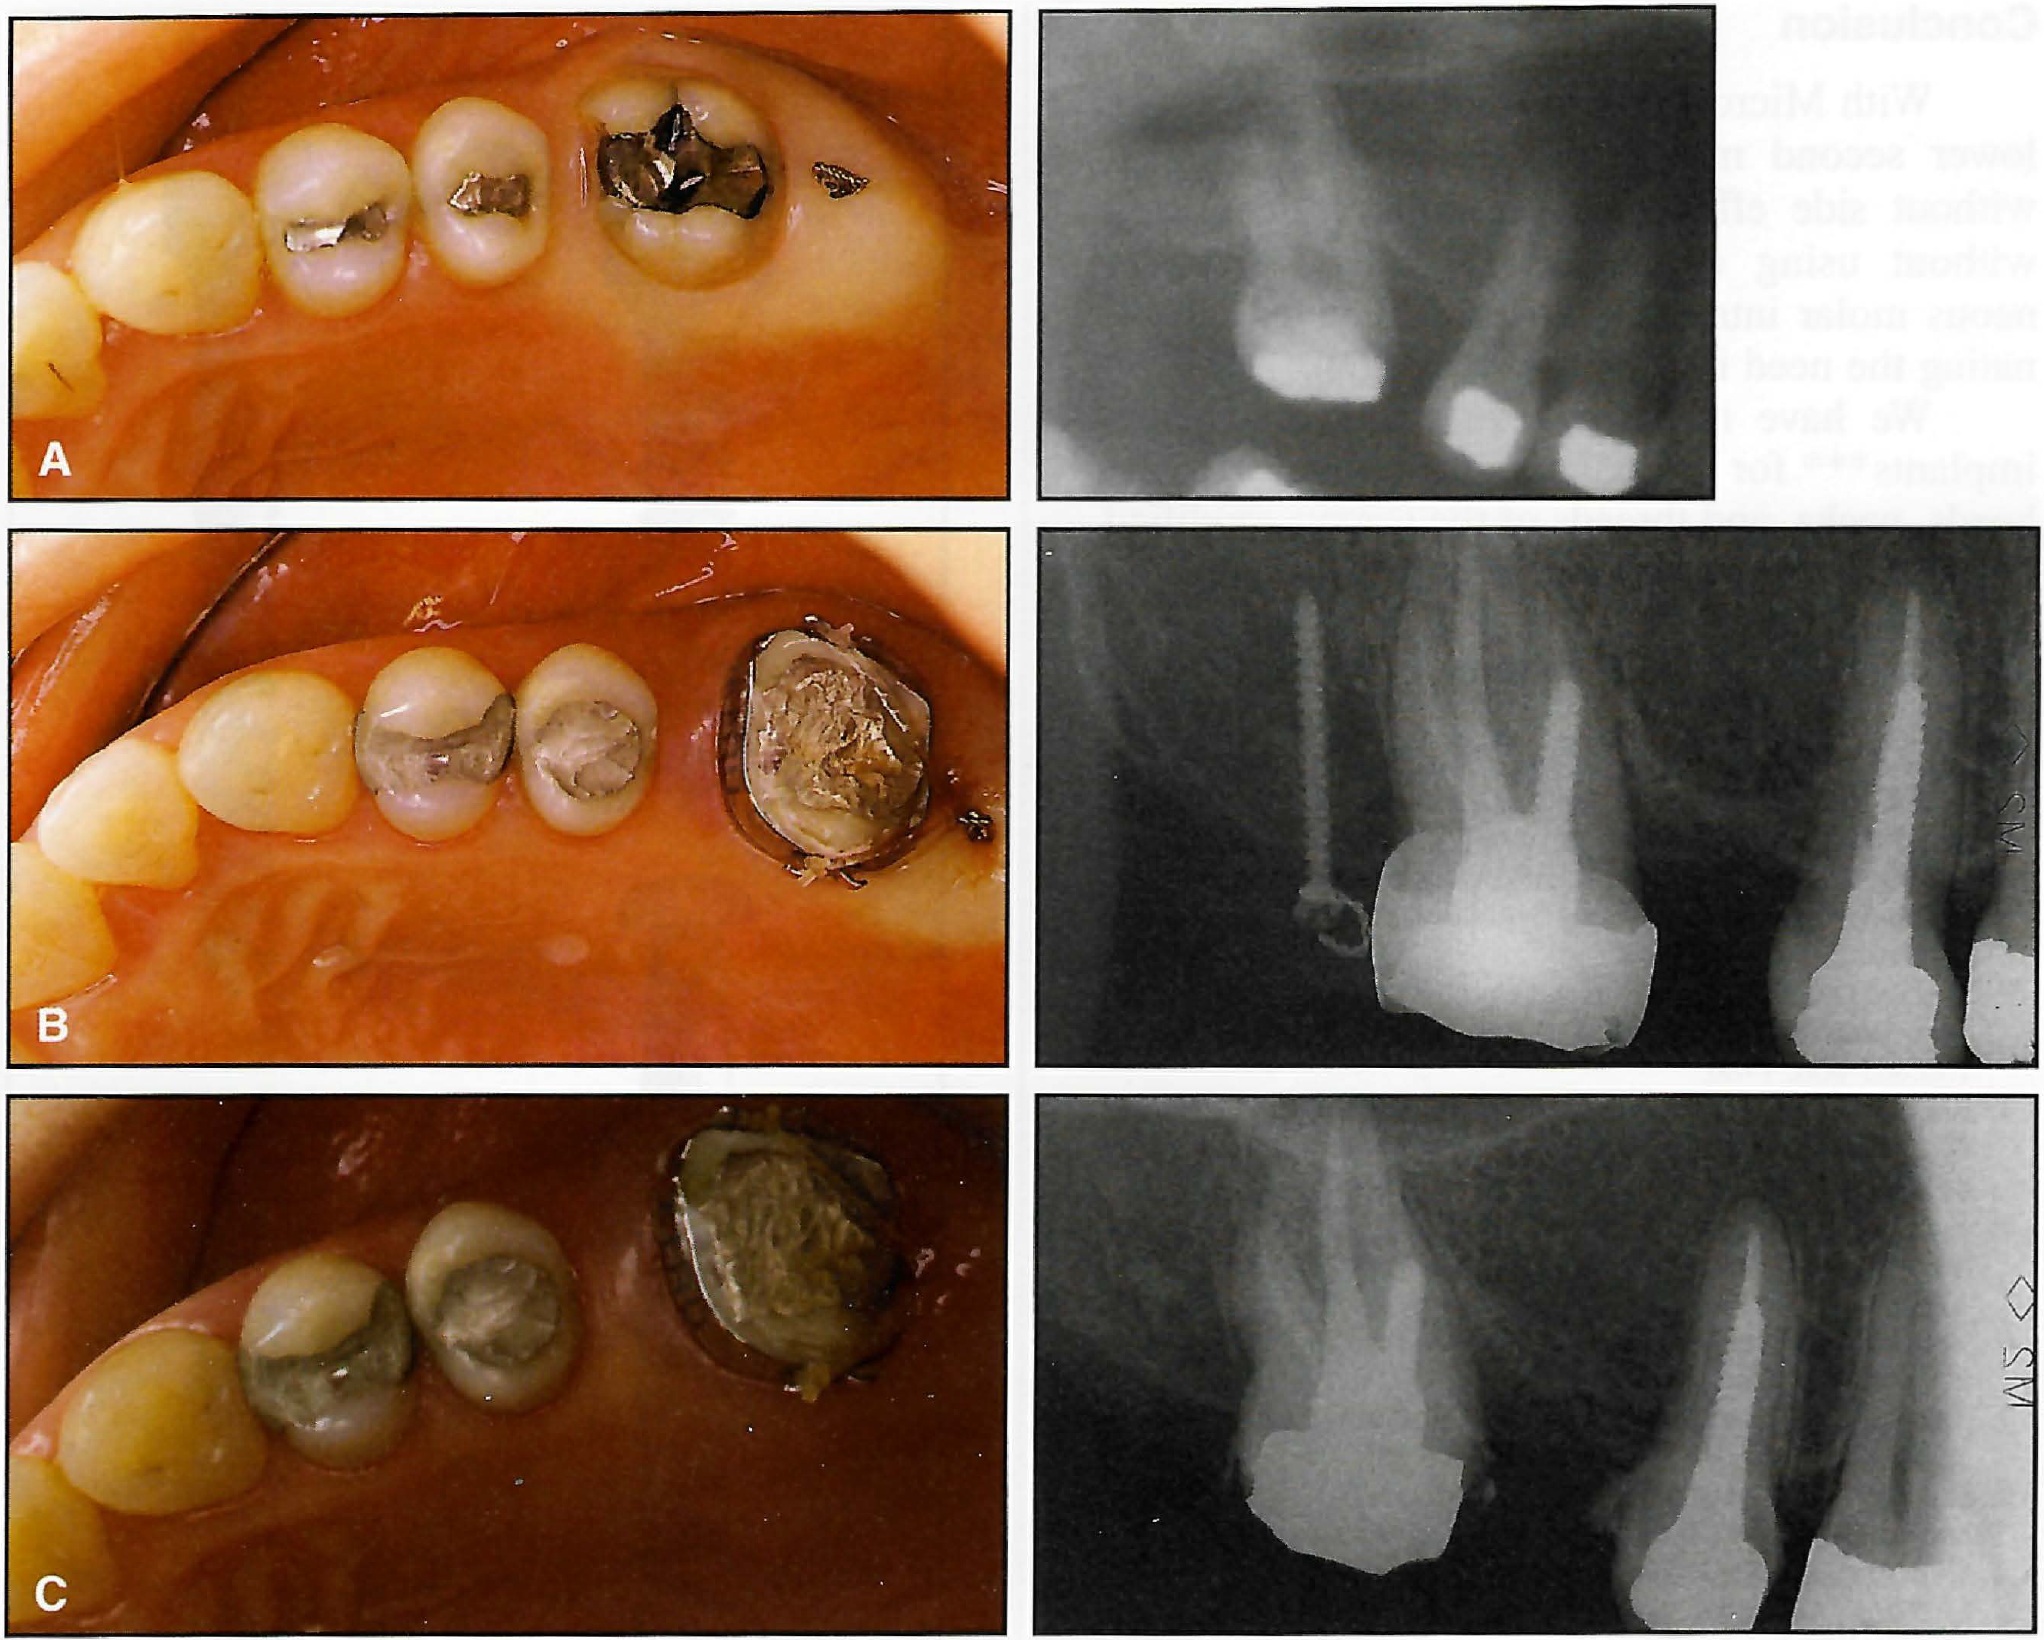

Even though the mandibular incisors were behind the APo line, the crowding was so severe that alignment of these teeth without extractions would have resulted in excessive proclination. Consequently, it was decided to extract the four first premolars to provide space without creating a bimaxillary protrusion.

Initial .016" Australian archwires with strong bite-opening bends mesial to the molar tubes were placed in both arches (Fig. 16A). The patient was instructed to wear light (1.5oz) Class II elastics full-time. Cooperation was poor during the first few months, but improved thereafter.

Within eight months, the overbite, overjet, and Class II molar relationship had been corrected. Stage III, delayed by the slow eruption of the maxillary second premolars, was begun after 17 months (Fig. 16B).

Eight months later, all root uprighting and torquing was complete and the appliances were removed (Fig. 16C). A tooth positioner was delivered for retention. Treatment was accomplished in about 26 months using only four straight archwires (two .016'' for Stage I and two .022" for Stages II and III).

Superimposition of pre- and post-treatment tracings showed that bite opening occurred without any opening of FMA or adverse rotation of the palatal plane (Fig. 15). The position of the upper incisors relative to APo improved from -2mm to +2mm, with a corresponding improvement in the facial profile (Fig. 14).

Fig. 16 Case 2. A. Six weeks after placement of initial .016" archwires with bite-opening bends. B. Beginning of Stage III. C. After 26 months of treatment.